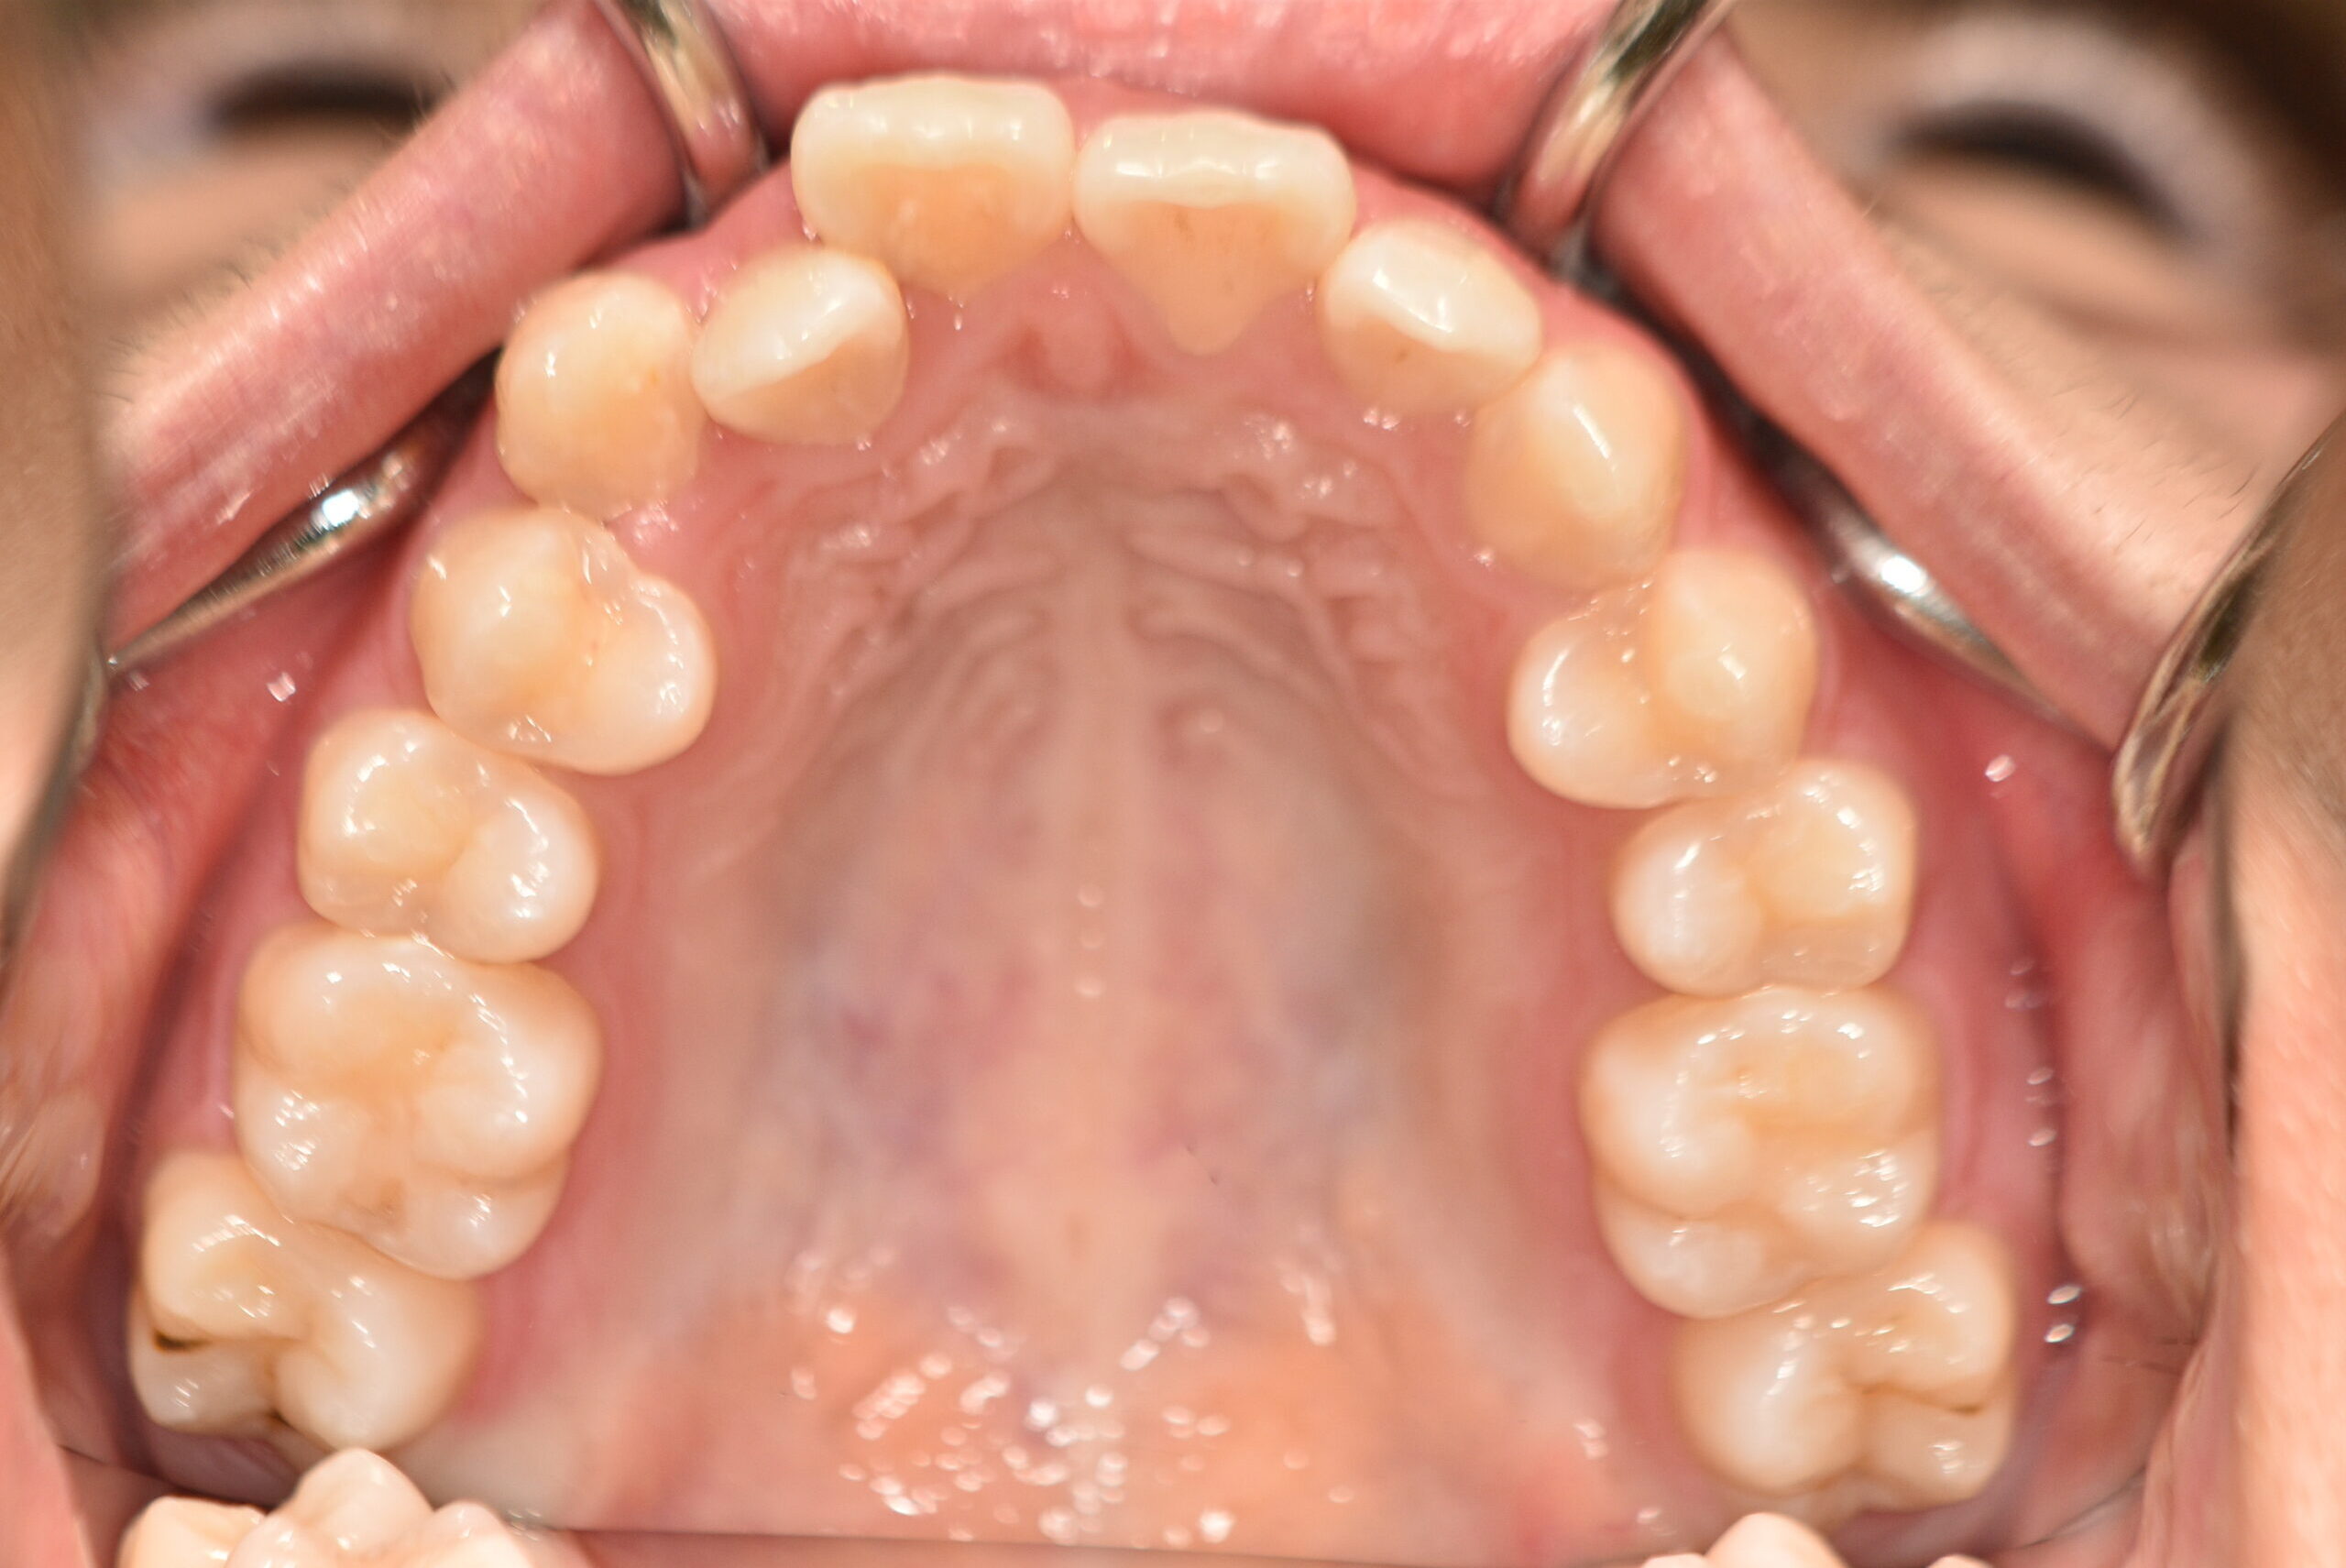

でっ歯(抜歯)【2247】

初診時

20歳 性 別 女性

治療期間 2年1ヶ月 費 用 矯正施術料:1,000,000円

治療内容の詳細 初診時20歳の女性で、出っ歯、歯のがたつきを気にされ来院しました。

検査の結果、上下顎前歯部叢生を伴うアングルⅠ級不正咬合と診断しました。

治療としては、上下左右第一小臼歯を抜歯の上、セルフライゲーションブラケット装置(デーモンシステム)と

マウスピース矯正装置(インビザライン)で配列を行いました。

この際、上顎に歯科矯正用アンカースクリューを設置し上顎前歯部後退時の土台としました。

治療期間は2年1ヶ月でした。